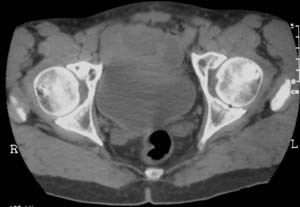

男,61岁,左侧髋关节疼痛,负重后更明显

现上传ct片

左侧股骨头增密,其内见有囊变密度减低区,关节面骨质硬化,关节间隙及髋臼无异示。考虑股骨头缺血坏死可能。建议mri检查。

我觉得股骨头未见到明显的问题,左侧股骨颈有卵圆形高密度影,考虑骨岛或骨梗死。

1\\左侧股骨颈有卵圆形高密度影,考虑骨岛或骨梗死。2\\由于临床症状疼痛,应该mri检查排除早期股骨头缺血坏死

左侧股骨颈处一卵圆形密度增高影,边界清,临近骨组织未见明显破坏.考虑为骨梗死,骨岛?